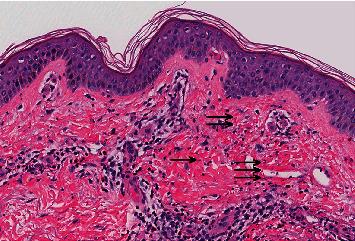

Leukocytoclastic vasculitis is a rare form of immune-mediated vasculitis that might be caused by infections or autoimmune diseases or might be precipitated by specific medications. We describe a 65-year-old patient, who was receiving vancomycin for a methicillin-sensitive permacath infection. Vancomycin was chosen due to medication non-adherence and the patient's desire to receive antimicrobial therapy in conjunction with his scheduled dialysis sessions. The patient's medical history was notable for untreated hepatitis C infection and end-stage renal disease, requiring hemodialysis three times a week. Vancomycin was administered during dialysis sessions. After one week of therapy, the patient developed bilateral lower extremity purpura. Skin biopsy was suggestive of leukocytoclastic vasculitis with an absence of intravascular thrombi. Serum cryoglobulins were negative, making cryoglobulinemia due to HCV infection unlikely. Following cessation of vancomycin therapy, the rash gradually disappeared with scarring in the form of post-purpuric hyperpigmentation. Despite its widespread use, vancomycin is a rare cause of leukocytoclastic vasculitis. Clinicians should keep in mind a wide range of differential diagnosis of bilateral lower extremity purpura as treatment differs depending on its underlying etiology.

白细胞破碎性血管炎是一种罕见的免疫介导性血管炎,可能由感染、自身免疫性疾病引起,也可能由特定药物诱发。我们描述了一名65岁的患者,他因耐甲氧西林的长期导管感染而接受万古霉素治疗。选择万古霉素是由于患者服药依从性差,且患者希望在定期透析期间接受抗菌治疗。患者的病史以未治疗的丙型肝炎感染和终末期肾病为显著特征,需要每周进行三次血液透析。万古霉素在透析期间给药。治疗一周后,患者出现双下肢紫癜。皮肤活检提示白细胞破碎性血管炎,无血管内血栓形成。血清冷球蛋白阴性,因此由丙型肝炎病毒感染引起冷球蛋白血症的可能性不大。停用万古霉素治疗后,皮疹逐渐消退,留下紫癜后色素沉着形式的瘢痕。尽管万古霉素广泛使用,但它是白细胞破碎性血管炎的罕见病因。临床医生应牢记双下肢紫癜的广泛鉴别诊断,因为治疗因潜在病因不同而有所差异。